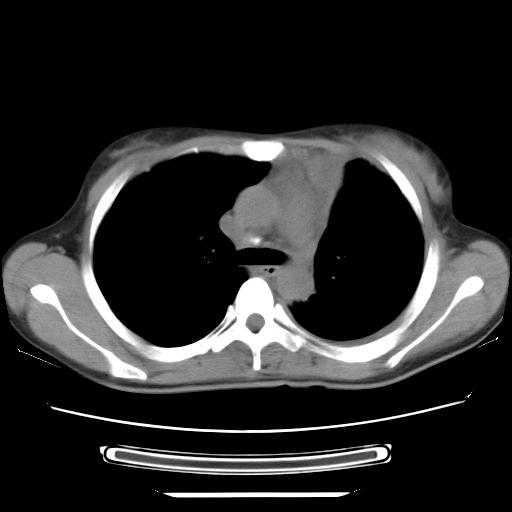

标题: CT21561:外院胸片提示胸腔积液,行CT检查。 [打印本页]

女,29岁,胸部不适,在外院胸片提示胸腔积液,到我院ct检查。

纵膈窗